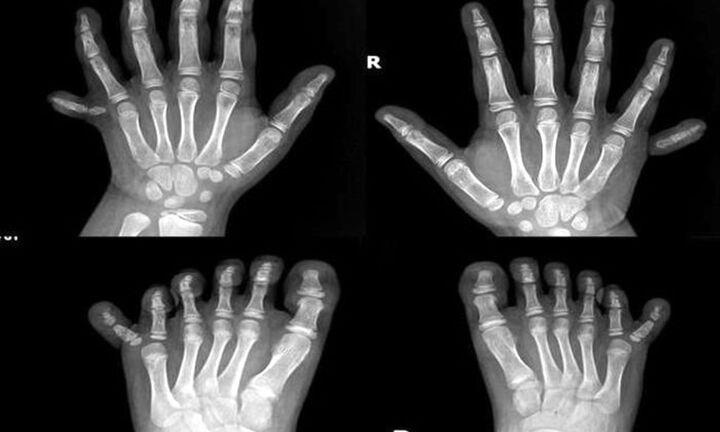

Bé gái có 12 ngón tay, 12 ngón chân được Bệnh viện Đa khoa Gia Đình Đà Nẵng phẫu thuật cắt bỏ thành công những ngón dư thừa.

Một bác sĩ đã đăng tấm hình này lên và nhấn mạnh rằng, tình trạng này không phải là hiếm hoi.